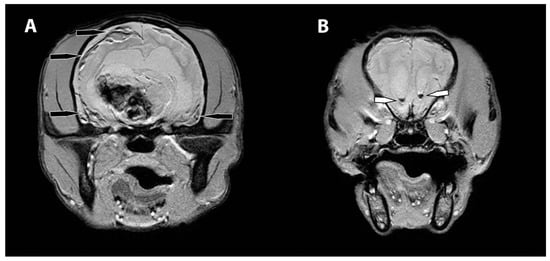

- Young, B.D.; Levine, J.M.; Porter, B.F.; Chen-Allen, A.V.; Rossmeisl, J.H.; Platt, S.R.; Kent, M.; Fosgate, G.T.; Schatzberg, S.J. Magnetic resonance imaging features of intracranial astrocytomas and oligodendrogliomas in dogs. Vet. Radiol. Ultrasound 2011, 52, 132–141. [Google Scholar] [CrossRef]

- Lee, Y.Y.; Van Tassel, P.; Bruner, J.M.; Moser, R.P.; Share, J.C. Juvenile pilocytic astrocytomas: CT and MR characteristics. AJR Am. J. Roentgenol. 1989, 152, 1263–1270. [Google Scholar] [CrossRef] [Green Version]

- Kumar, A.J.; Leeds, N.E.; Kumar, V.A.; Fuller, G.N.; Lang, F.F.; Milas, Z.; Weinberg, J.S.; Ater, J.L.; Sawaya, R. Magnetic resonance imaging features of pilocytic astrocytoma of the brain mimicking high-grade gliomas. J. Comput. Assist. Tomogr. 2010, 34, 601–611. [Google Scholar] [CrossRef]

- Nakano, Y.; Yamamoto, J.; Takahashi, M.; Soejima, Y.; Akiba, D.; Kitagawa, T.; Ueta, K.; Miyaoka, R.; Umemura, T.; Nishizawa, S. Pilocytic astrocytoma presenting with atypical features on magnetic resonance imaging. J. Neuroradiol. 2015, 42, 278–282. [Google Scholar] [CrossRef] [PubMed]